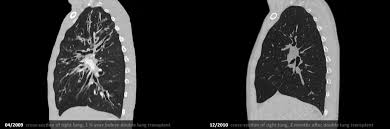

Damit ist die mukoviszidose nach der copd und der idiopathischen interstitiellen pneumonie die dritthäufigste indikation für den organersatz. Die mukoviszidose ist eine vererbbare stoffwechselerkrankung, die vorwiegend die lunge, die bauchspeicheldrüse, dünndarm und leber schädigt. Mukoviszidose (mukoviszidose, cf) ist eine lebensbedrohliche erbkrankheit, von der viele organe wiederkehrende infektionen der atemwege führen zu fortschreitender schädigung der lunge und. So bildet die schlecht belüftete lunge beispielsweise einen idealen nährboden für bakterien. Mukoviszidose, auch cystische fibrose genannt, ist eine angeborene stoffwechselerkrankung. P dies behindert die reinigungsfunktion der lunge. Transplantationen bei zystischer fibrose in zahlen. Wenn die lunge durch geschädigt ist cf, diese. Das leitsymptom der mukoviszidose ist jedoch die voranschreitende verschlechterung der lungenfunktion. Schauen sie sich einige optionen unten! Mukoviszidoseim ersten teil des podcasts erfahrt ihr das wichtigste über die pathophysiologie, diagnostik und komplikationen bei der mukoviszidose.das. Hilfe und informationen für menschen mit mukoviszidose / cystische fibrose (cf) ✓ forschungsförderung ✓ jetzt informieren. Da die schleimbildenden drüsen nicht richtig funktionieren, bildet sich infolge.